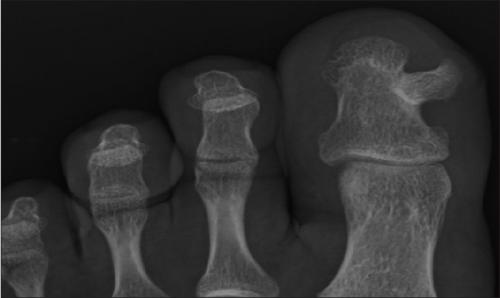

- Экзостоз большого пальца ноги рентген. Что такое экзостоз кости

Экзостоз большого пальца ноги рентген. Что такое экзостоз кости

Костно-хрящевой экзостоз – доброкачественное костно-хрящевое образование на наружной поверхности кости. Чаще всего оно обнаруживается еще в молодом возрасте до момента окончания роста скелета, в том числе у детей.

Экзостоз представляет собой нарост, образованный губчатой костью и имеющий кортикальный слой (прочную, твердую «оболочку»). Он может расти на ножке или крепиться к кости широким основанием. Снаружи костный нарост покрыт хрящевой тканью, имеющей много общего с суставными хрящами. Ее толщина не превышает 1 см. Верхний слой экзостоза еще называют хрящевой шапочкой.

Образование экзостоза ногтевого ложа протекает по-разному. В одних случаях костно-хрящевое выпячивание имеет небольшие размеры и годами никак не проявляется. Диагностируют такую патологию случайно — путем просмотра рентгеновских снимков, сделанных по причине иных заболеваний.